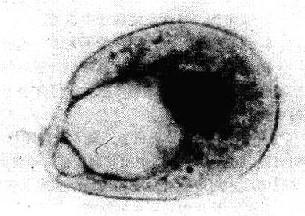

图19-3 退变的脱落细胞

子宫颈鳞癌细胸发生胸质空泡变性,空泡较大,说明细胸倾向于死亡